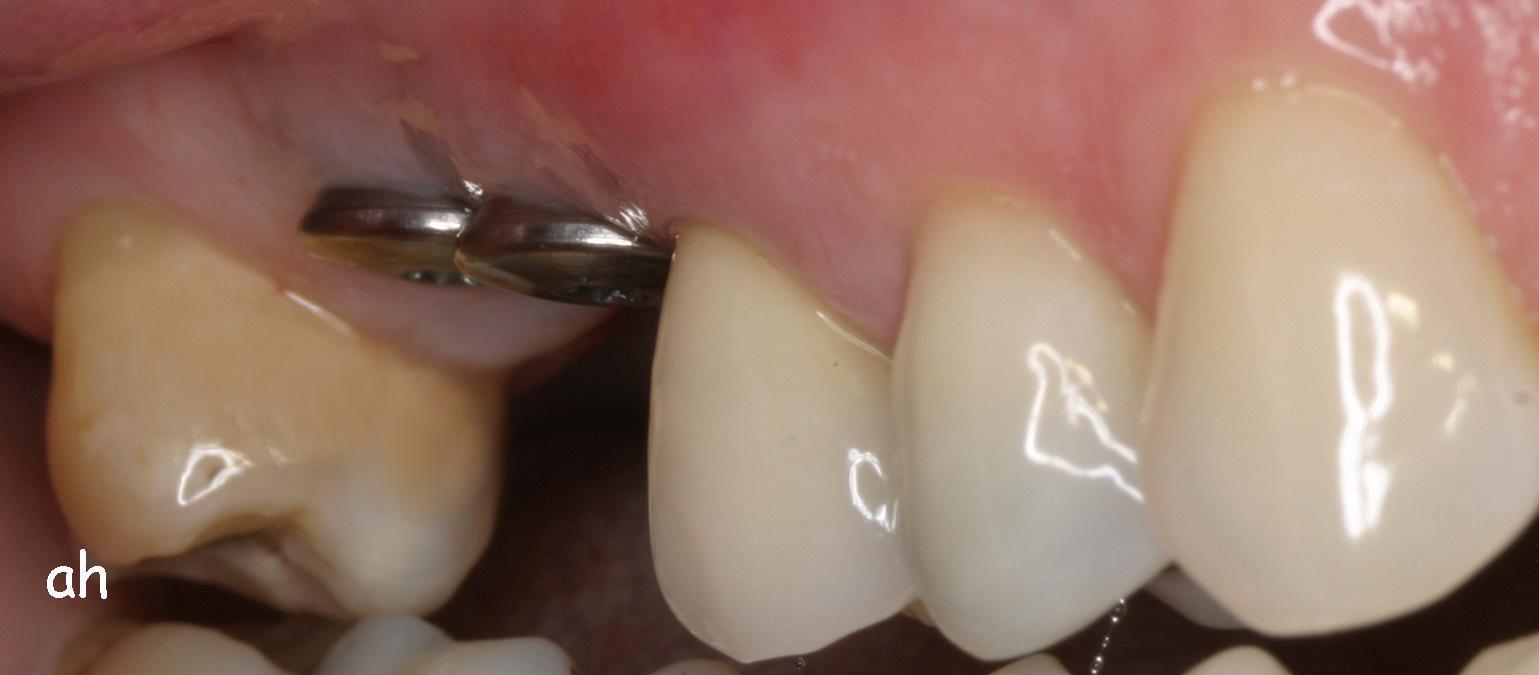

Exemple 3: Un implant à la place d'une incisive latérale supérieure droite. Sur cette image on voit le moignon en titane qui est vissé sur l'implant.

Exemple 3: Puis sur ce moignon, la couronne en céramique est scellée.

Exemple3: La couronne en place.